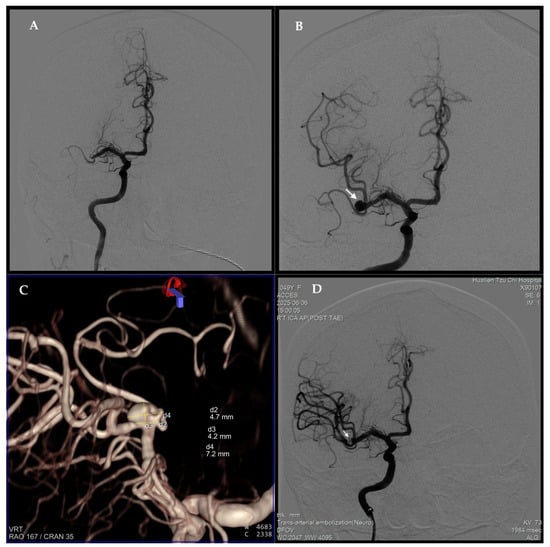

2. Case Report